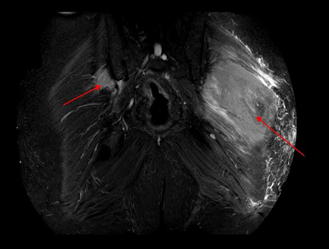

Figure 1a A soft tissue lesion measuring (AP *ML * SI) 9.8 x 5.9 x 9.5 cm seen in left Gluteus Maximus muscle (on MRI STIR coronal images).

MRI Gluteal region PD SPAIR PDW SPAIR (Proton Density Weighted Spectral Attenuated Inversion Recovery), a) Coronal images b) axial images showing large hyperintense soft tissue lesion in left gluteus maximus muscle (red arrow) with surrounding edema and lesion seen on right side in gluteus medius muscle.